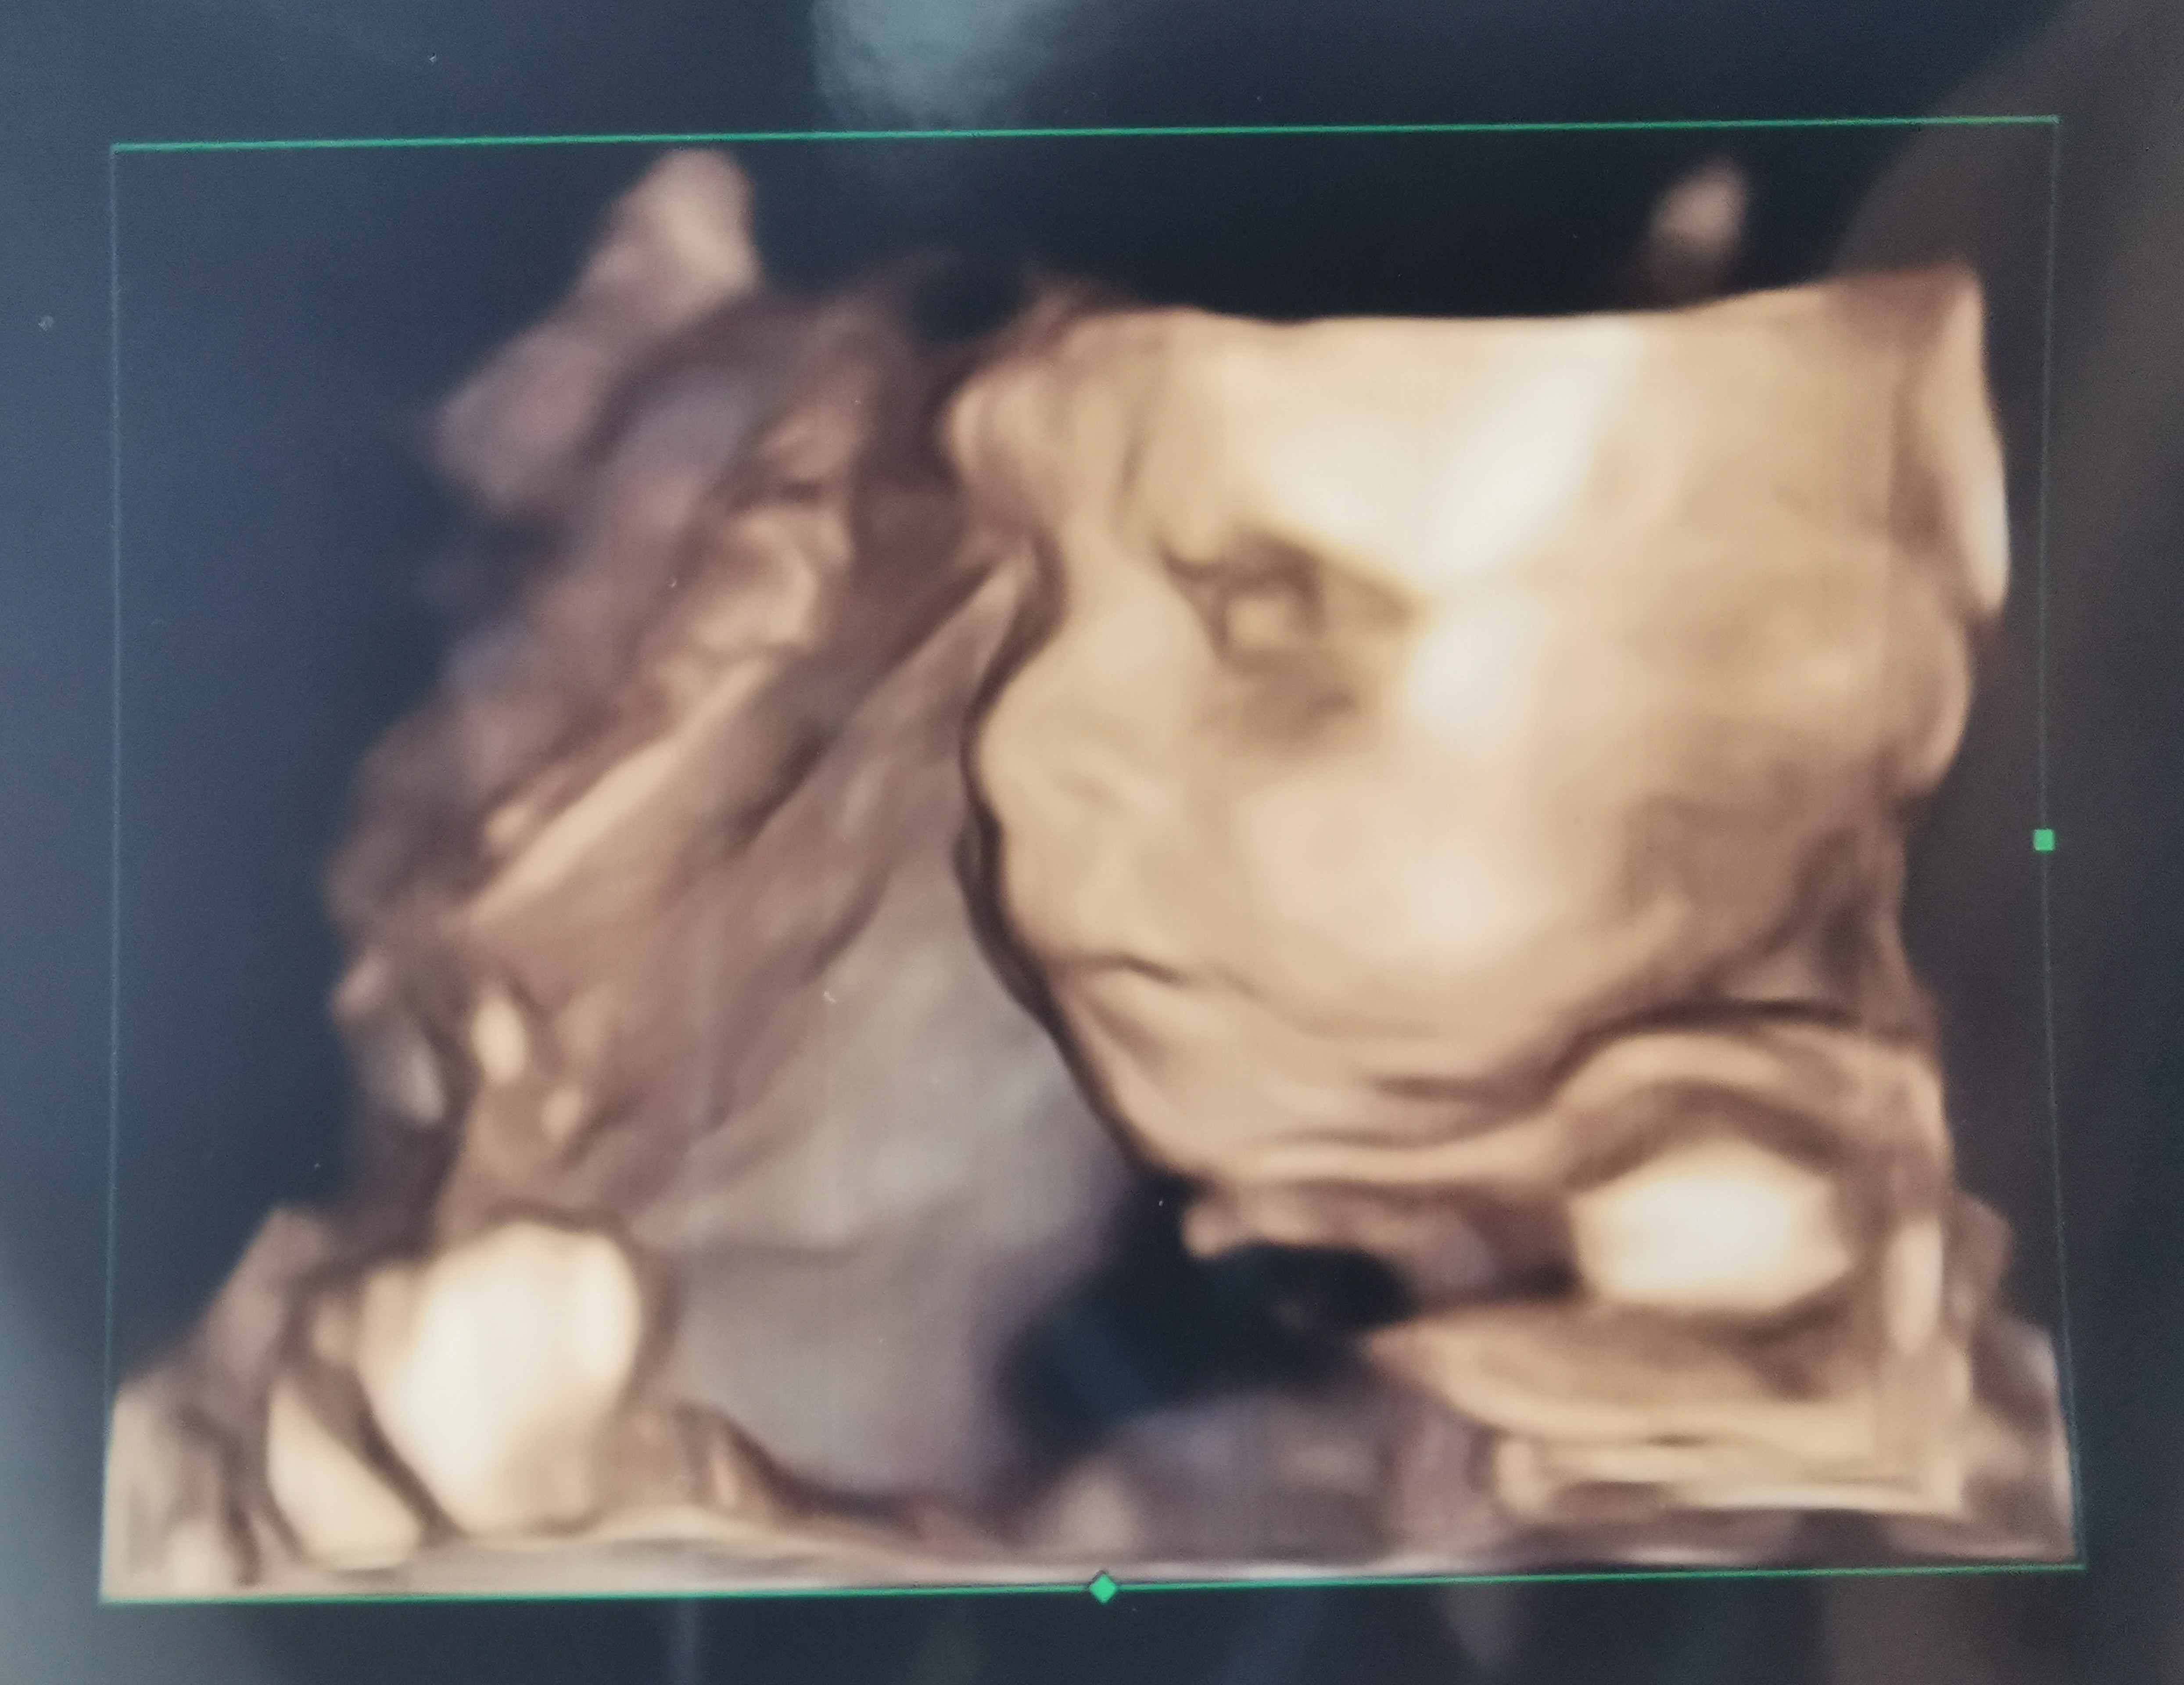

Hej, w porządku :) oprócz bólu ręki i lekkiego osłabienia wczoraj - wszystko gra! Tylko dzidzior jakiś taki wkurzony na zdjęciu 🤭

Załączniki

• IMG_20210716_174605~2.jpg

Ojjjj bedzie charakterek :D